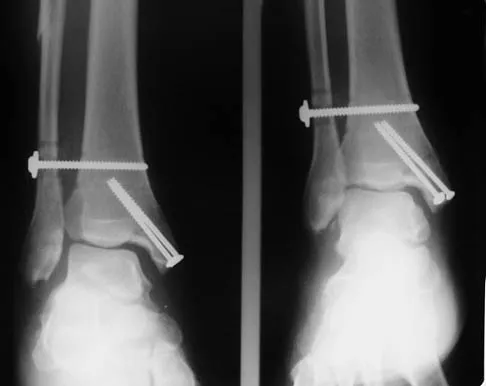

A patient with rheumatoid arthritis with both ankle and subtalar involvement was treated as shown in Figures 11a and 11b. What complication is unique to this type of fixation?

Explanation

The interlocking screws at the proximal end of the rod can act as a stress riser and lead to fracture. Postoperative pain at this level should prompt inclusion of this diagnosis in the differential. Removing the screws following bone union can decrease the chances of this occurring. A short rod that avoids the diaphyseal area may also be beneficial. Rotatory deformity is controlled by the perpendicularly oriented distal transfixion screws. Talar osteonecrosis would be unusual since the dissection can be minimized with an intramedullary rod. Any type of hardware can fail if the construct does not lead to a solid arthrodesis. Nunley JA, Pfeffer GB, Sanders RW, et al (eds): Advanced Reconstruction: Foot and Ankle. Rosemont, IL, American Academy of Orthopaedic Surgeons, 2004, pp 236-237. Thordarson DB, Chang D: Stress fractures and tibial cortical hypertrophy after tibiotalocalcaneal arthrodesis with an intramedullary nail. Foot Ankle Int 1999;20:497-500.